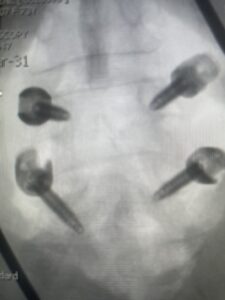

Another patient is a 62 year-old female with progressive low back pain and right leg pain and numbness that radiates to the top of her foot. She tried physical therapy and epidural injections. MRI demonstrated severe L3-4 stenosis and a grade 1 spondylolisthesis (Fig 4). There was L5-S1 and L4-5 disc collapse with modic end-plate changes. Biomechanically because of the significant degeneration of these disc spaces which stiffened the L4-S1 segment more stress was placed on the L3-4 segment, resulting in significant premature degeneration and compensatory stenosis and segmental instability. The MRI also showed pathologically, because of the slip, the L3 inferior processes were more anteriorly oriented and hence contributing to the majority of the lumbar canal compromise. Note the more sagittally-oriented facets in this case compared to the prior case (Fig 5). The patient underwent a decompressive laminectomy with attention of removing the inferior processes of L3 to fully decompress the canal. We also performed an L3-4 fusion with instrumentation (Fig 6). The patient had an uneventful postoperative course with improvement of leg pain. Of note with relief of the disabling leg pain patients are generally very happy. Patients can often manage their low back pain; it is the leg pain that they just can’t tolerate.

Fig 6: AP and lateral fluoroscopic images demonstrating pedicle screw placement in L3-4 fusion for spondylolisthesis.